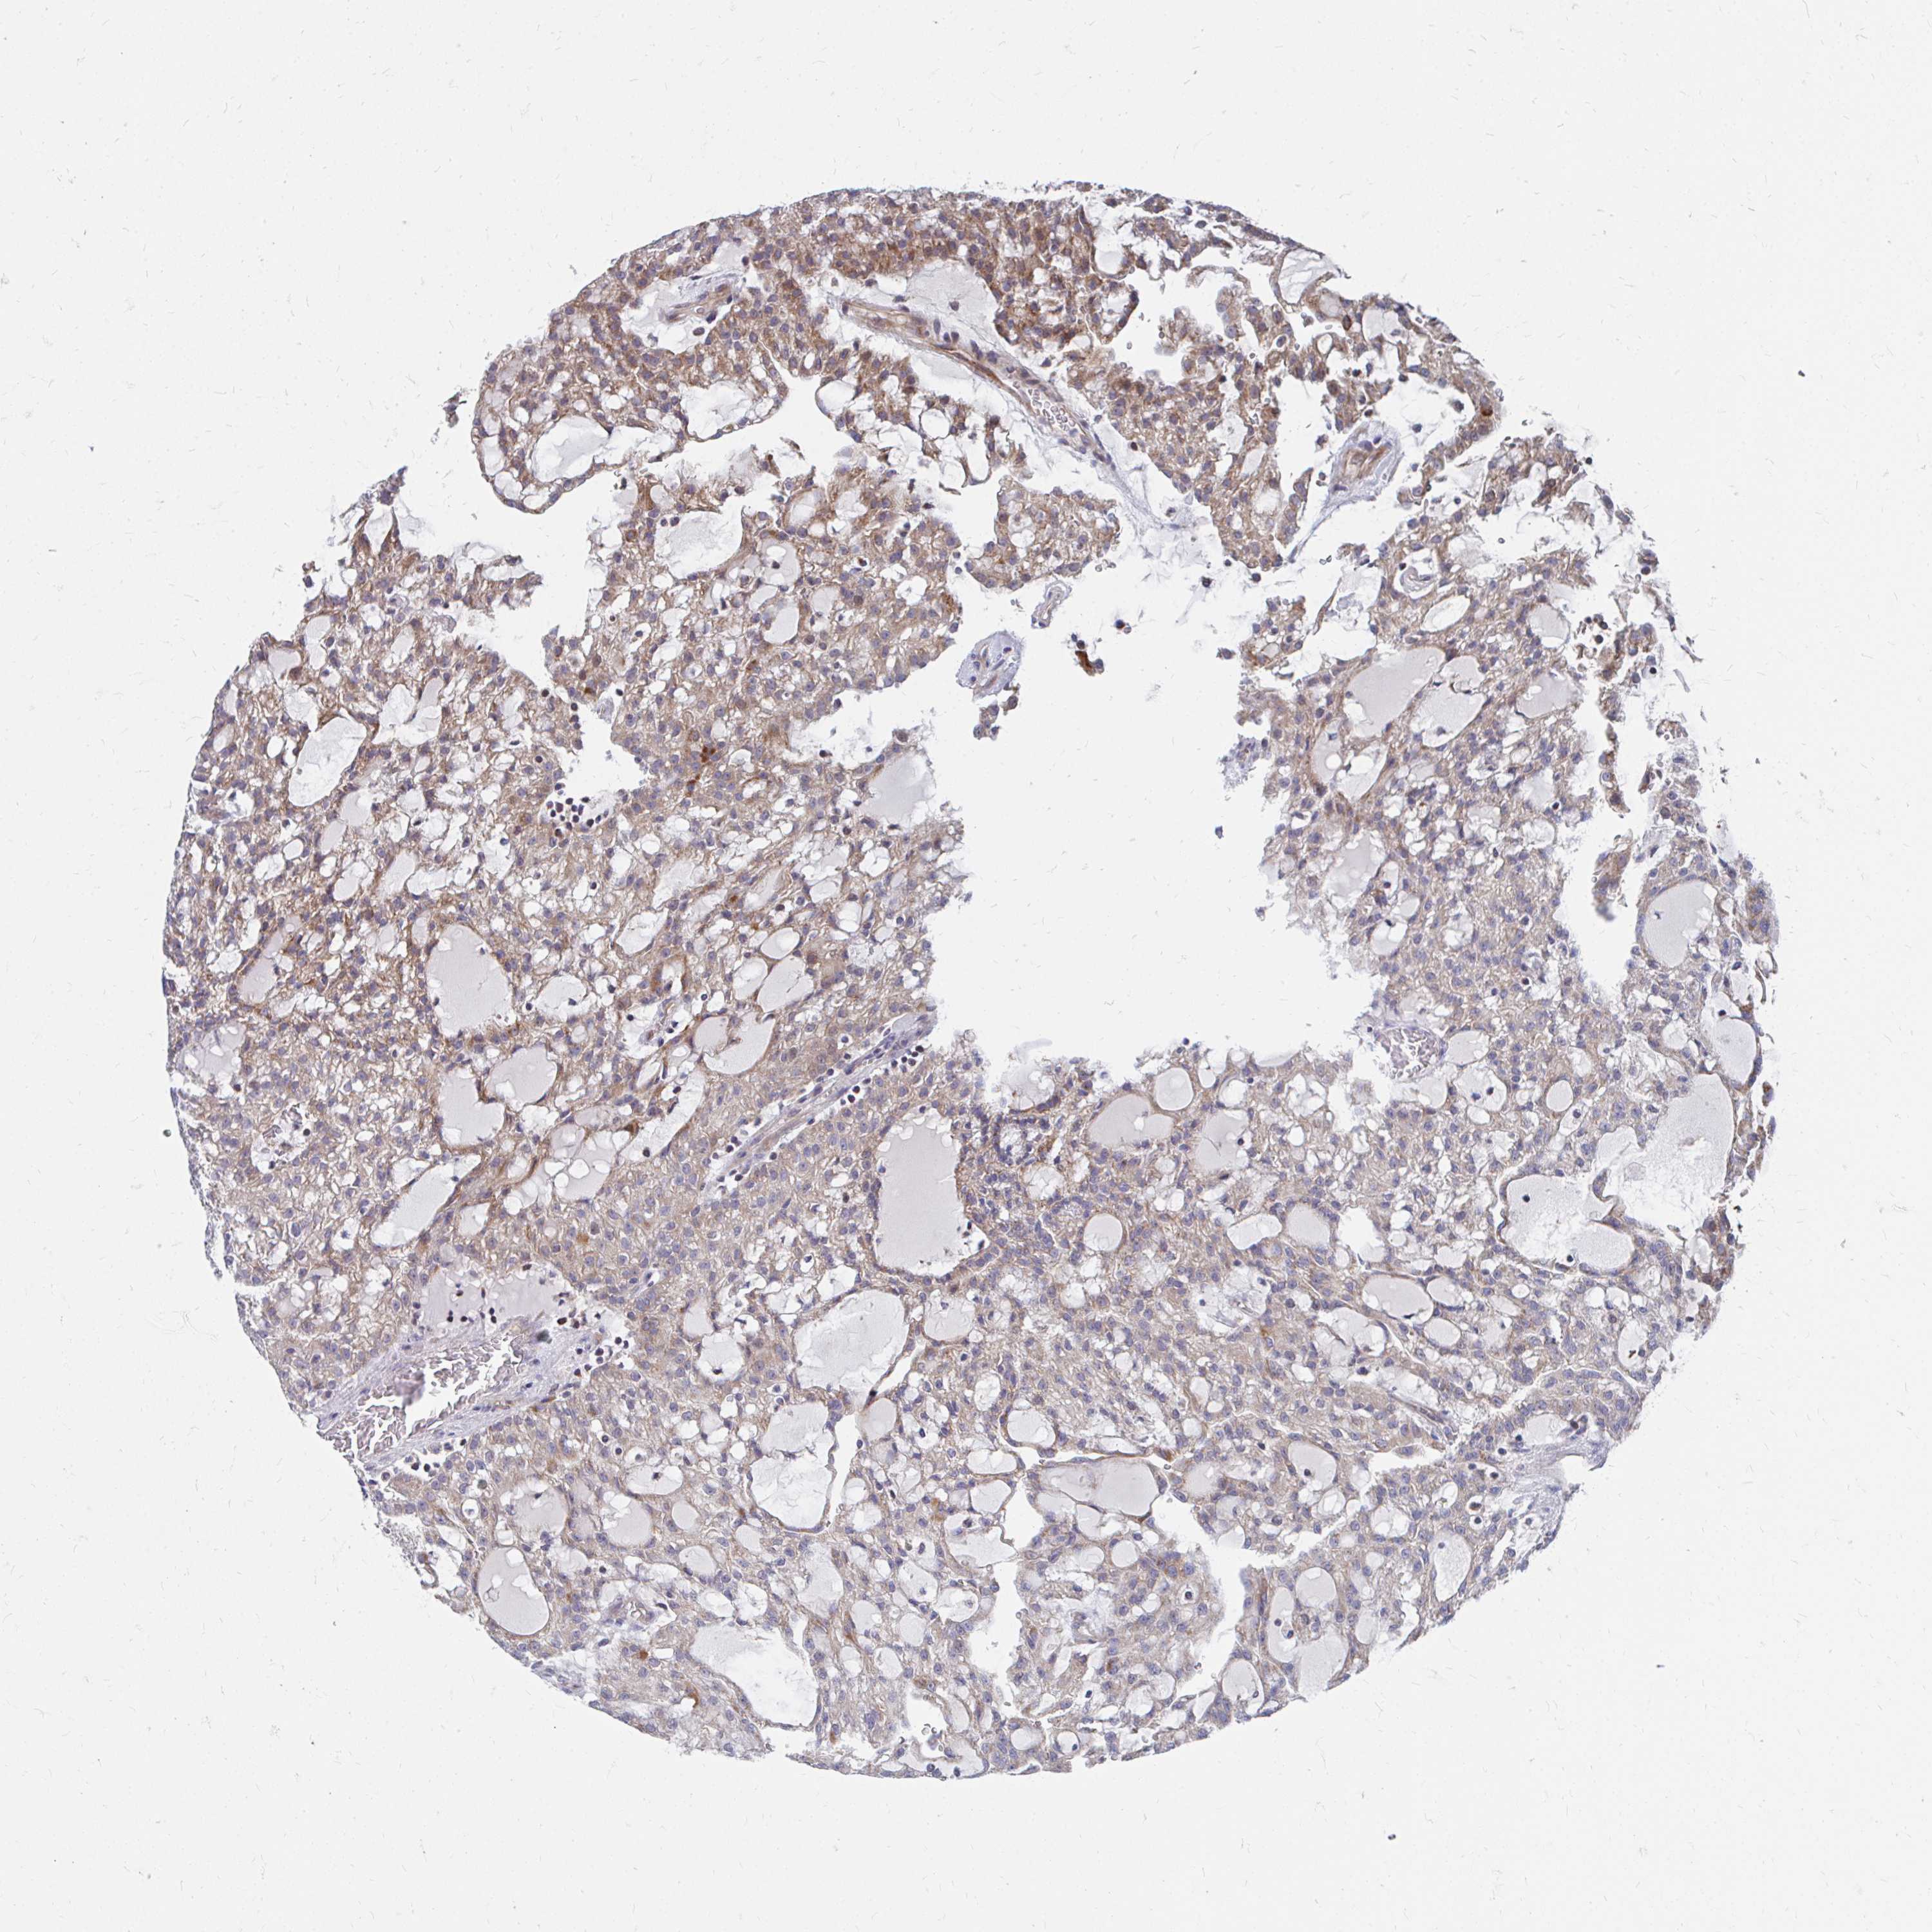

KIDNEY RENAL CLEAR CELL CARCINOMA (VALIDATION) - Interactive survival scatter ploti

The Survival Scatter plot shows the clinical status (i.e. dead or alive) for all individuals in the patient cohort, based on the same data that underlies the corresponding Kaplan-Meier plots. Patients that are alive at last time for follow-up are shown in blue and patients who have died during the study are shown in red.

The x-axis shows the expression levels (FPKM) of the investigated gene in the tumor tissue at the time of diagnosis. The y-axis shows the follow-up time after diagnosis (years). Both axes are complimented with kernel density curves demonstrating the data density over the axes. The top density plot shows the expression levels (FPKM) distribution among dead (red) and alive patients (blue). The right density plot shows the data density of the survived years of dead patients with high and low expression levels respectively, stratified using the cutoff indicated by the vertical dashed line through the Survival Scatter plot. This cutoff is automatically defined based on the FPKM cutoff that minimizes the p-score. The cutoff can be changed by dragging the vertical line or by entering a cutoff value in the square labeled "Current cut-off".

Under the Survival Scatter plot the p-score landscape (black curve; left axis) is shown together with dead median separation (red curve; right axis). Dead median separation is the difference in median mRNA expression between patients who have died with high and low expression, respectively. It is calculated as follows: median FPKM expression of dead patients with high expression - median FPKM expression of dead patients with low expression. This is intended to aid the user in visually exploring custom cutoffs and the associated p-scores and dead median separation.

Individual patient data is displayed and can be filtered by clicking on one or more of the category buttons on the top of the page. Categories describing expression level and patient information include: high, low, alive, dead, female, male and tumor stages. The scale of the x-axis can be toggled between linear and log-scale by clicking on the "x log" button. Mouse-over function shows TCGA ID, patient information and mRNA expression (FPKM) for each patient.

& Survival analysisi

Kaplan-Meier plots summarize results from analysis of correlation between mRNA expression level and patient survival. Patients were divided based on level of expression into one of the two groups "low" (under cut off) or "high" (over cut off). X-axis shows time for survival (years) and y-axis shows the probability of survival, where 1.0 corresponds to 100 percent.

PEX3 is not prognostic in Kidney Renal Clear Cell Carcinoma (validation)

Best expression cut offi

: 10.54

P scorei

N/A

Average pTPM 13.5

Number of samples 100